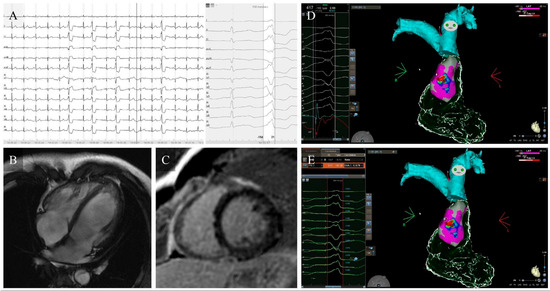

Premature Ventricular Complex-Induced Cardiomyopathy, a Review: Current Insights, Diagnostic Challenges, and Therapeutic Strategies

Premature Ventricular Complexes (PVCs) are among the most frequent ventricular arrhythmias observed in daily cardiology practice. Although often benign, sustained high ectopic activity can result in left ventricular dysfunction known as PVC-induced Cardiomyopathy (PVC-CMP), a condition that is frequently reversible when the arrhythmia [...] Read more.

Premature Ventricular Complexes (PVCs) are among the most frequent ventricular arrhythmias observed in daily cardiology practice. Although often benign, sustained high ectopic activity can result in left ventricular dysfunction known as PVC-induced Cardiomyopathy (PVC-CMP), a condition that is frequently reversible when the arrhythmia is effectively suppressed. The underlying mechanisms are multifaceted, involving electromechanical dyssynchrony, contractile inefficiency, abnormal calcium cycling, neurohormonal activation, and progressive structural remodeling. The likelihood of developing PVC-CMP varies among individuals and is influenced by electrophysiological and structural factors. Diagnosis relies on prolonged rhythm monitoring, comprehensive multimodality imaging, and demonstration of ventricular recovery after reducing the ectopic burden, which, in turn, confirms causality. Over the past decade, major advances in electrocardiographic mapping, cardiac imaging, and ablation therapy have transformed this field, demonstrating excellent efficacy and safety profiles. In parallel, artificial intelligence and computational mapping are emerging as powerful tools for prediction and procedural guidance. Recognition of PVC-CMP as a distinct, treatable cardiomyopathy highlights the importance of early detection and individualized therapy, offering the prospect of complete functional recovery and the prevention of heart failure progression. Full article

Figure 1